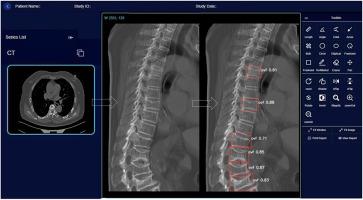

An automated sagittal Central Slab reconstruction (CSR) method for CT axial images was developed. For reference VF reading, VFs inclusive of those of with <20 % vertebral height loss and those of endplate fracture with minimal vertebral height loss were identified. VFs were also differentiated from osteoarthritic wedging and endplatitis short vertebrae. Prior knowledge of VF detection models for lateral radiograph were transferred to a new ‘Ofeye 3.0’ model optimized for VF detection on CT image. Training CT images were obtained from nine centers, totaling 3313 cases without VF and 835 cases with VF. For external validation, CT images were from five centers totaling 732 cases without VF and 224 cases with VF.

The automated CSR method showed advantages in demonstrating structural changes of the endplate and adjacent structures. For detecting VF in chest/abdominal CT scans, counting case-by-case and compared with the reference reading, the average performance of Ofeye 3.0 was accuracy 0.967, sensitivity 0.906, and specificity 0.986. Most of false negative or false positive cases were minimal or mild VF, or with image artifacts, or with VF close to the peripheral of CSR images.